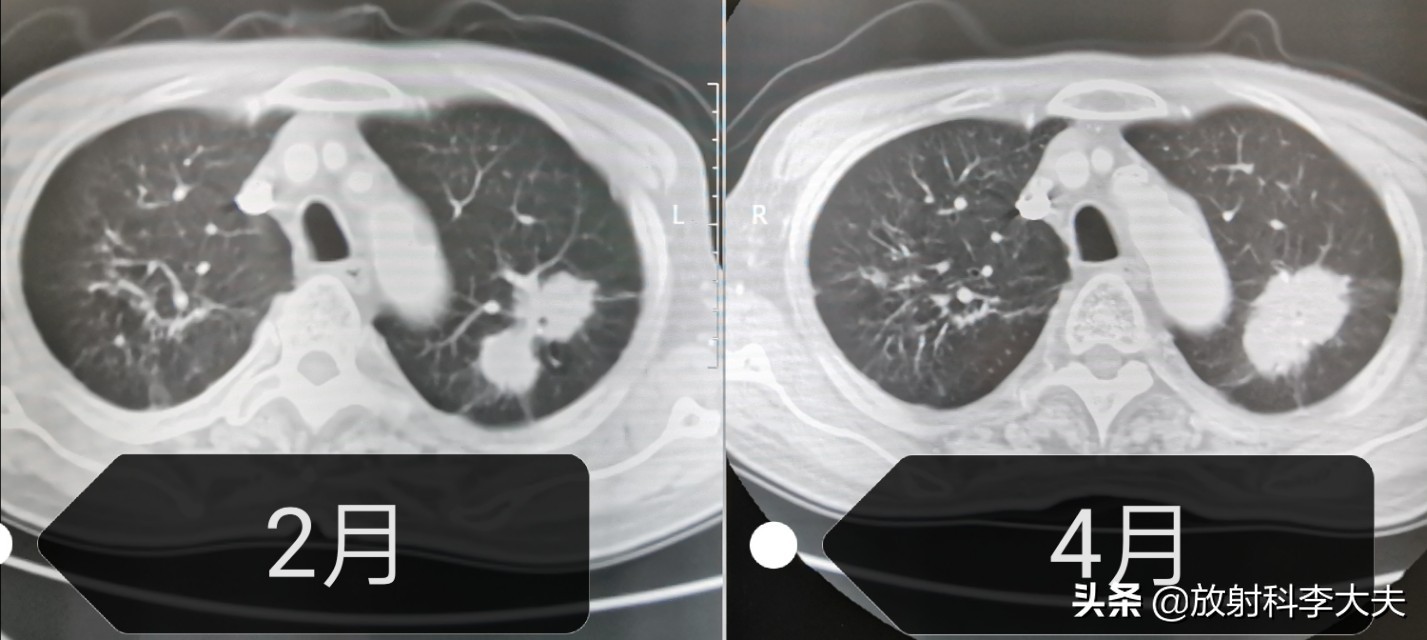

病人回家吃了两个月的抗痨药,四月份回来复查。

哑铃长大了,分叶征更明显了。两个月的时间,病变增大,说明抗结核无效,基本上排除结核,肺癌可以考虑了。

随后病人进行了穿刺活检,病理结果是:低分化腺癌。